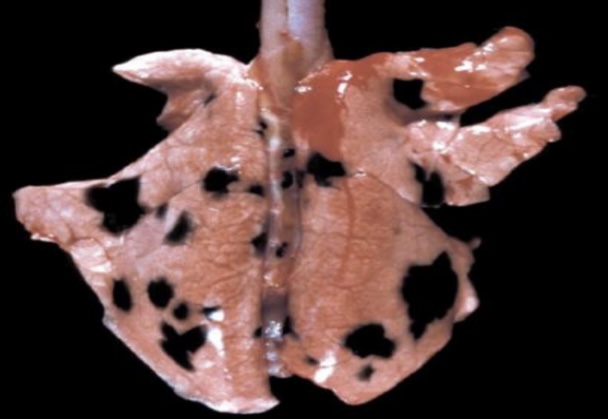

Anthracosis